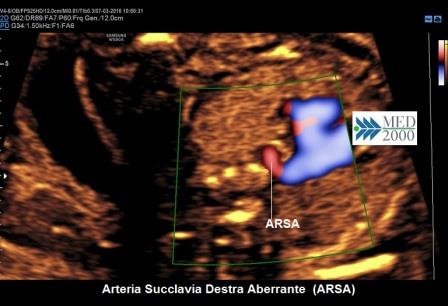

La scansione ecografica per la diagnosi di ARSA è data dalla immagine

a "V" determinata dalla congiunzione a livello duttale tra Arteria

Polmonare ed Aorta ( Paladini D.; 2011 ).

La velocità di flusso attraverso l'ARSA è più bassa rispetto ai grossi vasi per cui per ottenere una ottimale visualizzazione dell'arteria anomala è opportuno ridurre la PRF di circa 20 cm/sec. se si usa il Color-Doppler oppure utilizzare il Power-Doppler.

In questa scansione (arteria polmonare più vicina alla sonda) l'ARSA si presenta come un vaso colorato in blu che origina a 90° dalla base della V per dirigersi, passando dietro la trachea, verso la spalla destra del feto.

Se per la posizione del feto l'immagine a "V" è posta in modo che è l'aorta ad essere più vicina alla sonda, l'ARSA assume la colorazione in rosso.